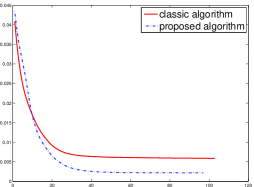

Noised projection data: For the noised projection data, the iteration processes were terminated when for 82 and 112 projections. The reconstruction images were given in Fig. 7. Table 4 showed the MSEs, iterations and running time of program of the results of images in Fig. 7.

By comparing the images in Fig. 6, 7 and numbers in Table 3, 4, we can obtain the same conclusions that the proposed perturbation can not only improve qualities of reconstructed images, but also can accelerate the convergent speed. However, we can observe that the reconstruction images suffer from artifacts regardless of the classic and the proposed algorithm when the projections is inadequate.